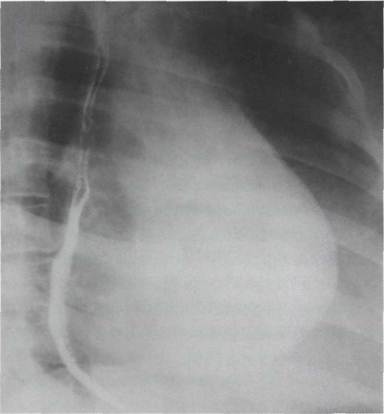

Правая (первая) косая проекция

При митральной недостаточности, в отличие от митрального стеноза, в правой передней косой проекции нет резкого расширения дуги конус пульмоналис и между передним контуром сердца и реберной границей остается свободным широкое клиновидное пространство. При митральной недостаточности контрастированный пищевод в правом переднем косом положении отклоняется кзади по дуге большого радиуса (рис. 35). Из-за резкого увеличения левого предсердия и атрофических изменений клетчатки средостения пищевод приобретает чрезмерную подвижность. При этом в течение одной рентгеноскопии он может изменять свое положение. Это явление носит название «соскальзывания» пищевода с левого предсердия.

Отклонение контрастированного пищевода при митральной недостаточности в правой косой проекции

При выраженной митральной недостаточности увеличено левое предсердие, что еще более четко выявляется в косых положениях с одновременный приемом бария. В отличие от митрального стеноза, пищевод отклоняется кзади предсердием по дуге большого радиуса (8- 10 см).